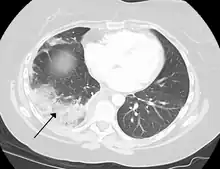

Chest CT (axial lung window)

Chest CT (coronal lung window)- Chest CT (axial lung window)

Lung cancer can either arise directly from lung tissue or as a result of metastasis from another part of the body. There are two main types of primary tumour described as either small-cell or non-small-cell lung carcinomas. The major risk factor for cancer is smoking. Once a cancer is identified it is staged using scans such as a CT scan and a sample of tissue from a biopsy is taken. Cancers may be treated surgically by removing the tumour, the use of radiotherapy, chemotherapy or a combination, or with the aim of symptom control.[76] Lung cancer screening is being recommended in the United States for high-risk populations.[96]